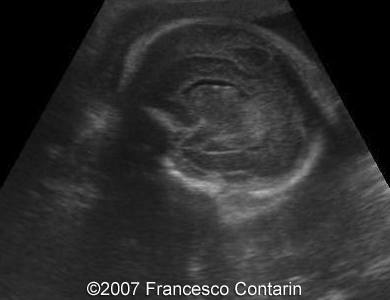

Images 9, 10. 29th week of pregnancy -  fetal ascites (left); and transverse plane through narrow thorax (right).

9

10